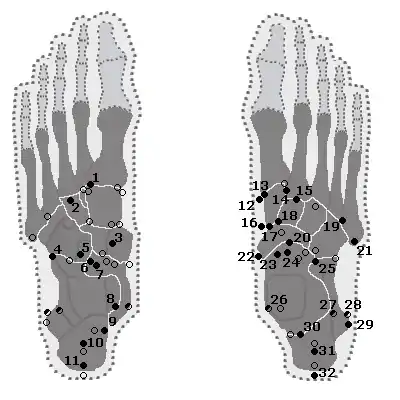

Pied

| Os | Prévalence [9] |

|---|---|

| Os sésamoïdes | |

| Sésamoïdes au niveau de l'articulation articulation métatarso-phalangienne de l'hallux | Toujours présente |

| Sésamoïde du deuxième métatarsien | 0,4% |

| Sésamoïde du troisième métatarsien | 0,2% |

| Sésamoïde du quatrième métatarsien | 0,1% |

| Sésamoïdes du cinquième métatarsien | 4,3% |

| Sésamoïde de l'articulation interphalangienne de l'hallux | 2 à 13 % |

| Os non sésamoïdes | |

| Os trigone (non visible dans la projection dorso-plantaire) | 7 à 25 % |

| Os peroneum | Jusqu'à 26% |

| Os naviculaire accessoire | 2 à 21 % |

| Os intermetatarseum | 1 à 13 % |

| Os supranaviculare | 1,0 à 3,5 % |

| Os calcanéus secondaire | 0,6 à 7 % |

| Os supratalare | 0,2 à 2,4 % |

| Os vésalianum | 0,1 à 1 % |

| Os talotibiale | 0,5% |